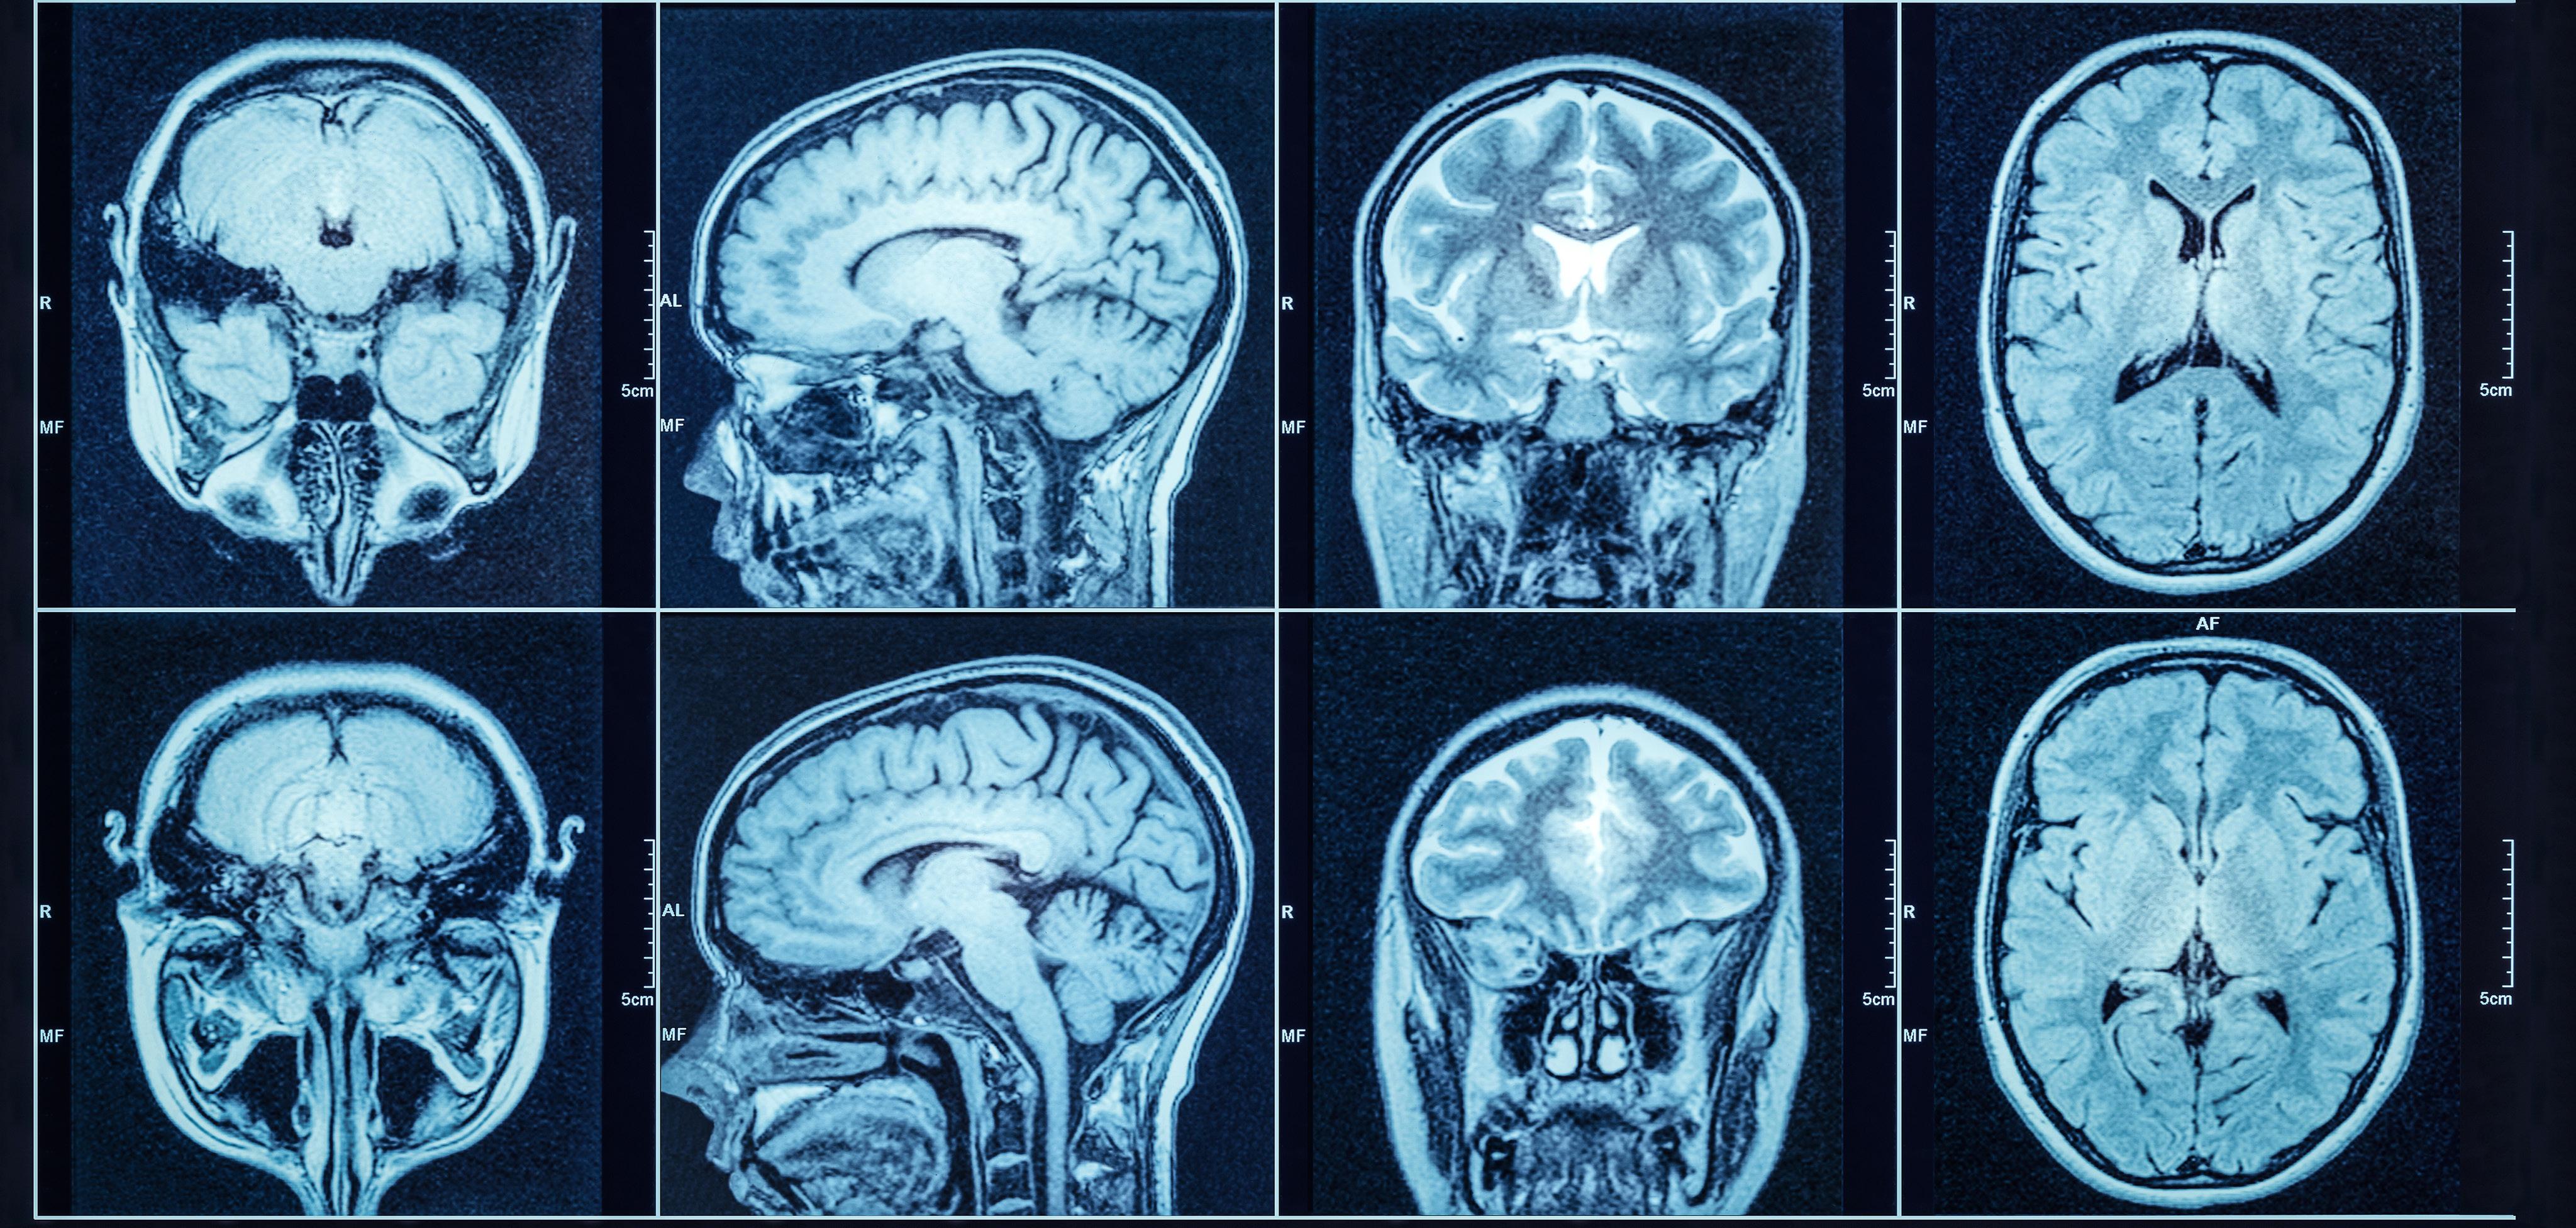

WHOLE BODY MRI SCREENING

Whole-body MRI is very effective in detecting cancer at an early stage. Large studies have shown that 1-2% of people over 40 have cancer on whole-body MRI screening.

Early diagnosis can make treatment more effective.

Over 2,000 images of your body.

Head and neck, including the brain and skull.

Chest, including lungs.

Abdomen and pelvis: including the pancreas, liver, gallbladder, kidneys, adrenal glands, bladder.

Reports by expert UK radiologists.

No exposure to X-rays or radiation.

Can detect cancer before symptoms appear.

Comfortable scanning environment.

Doctor's guidance at all steps for positive results.

All scans are at imaging centres in Central London. Chosen for their expert radiologists.